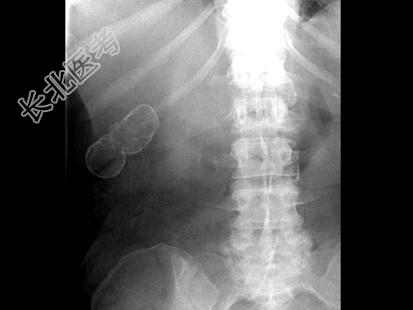

- 单项选择题女,39岁, 右上腹部隐痛,有慢性胆囊炎史, 曾经做过口服胆囊造影,胆囊显影差, X线检查如图,最可能的诊断是 ( )

A、急性胆囊炎

B、慢性胆囊炎

C、胆囊结石

D、瓷样胆囊

E、胆囊结核